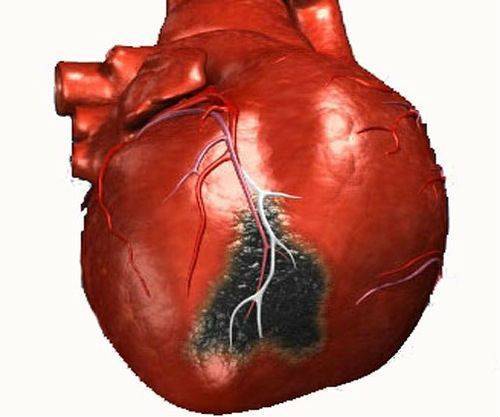

Абдоминальная форма инфаркта миокарда — чаще связана с локализацией ишемии в зоне задней стенки левого желудочка. Боли сжимающего, жгучего или давящего типа возникают внезапно, локализуются в эпигастрии, иррадиируют в живот, спину, лопатку, затрудняют дыхание.

На ЭКГ возникают признаки ишемии, блокад, аритмии. Заболевание настолько известно хирургам, что ни один опытный врач не приступит к операции по поводу холецистита, пока не будет проведено ЭКГ-исследование.